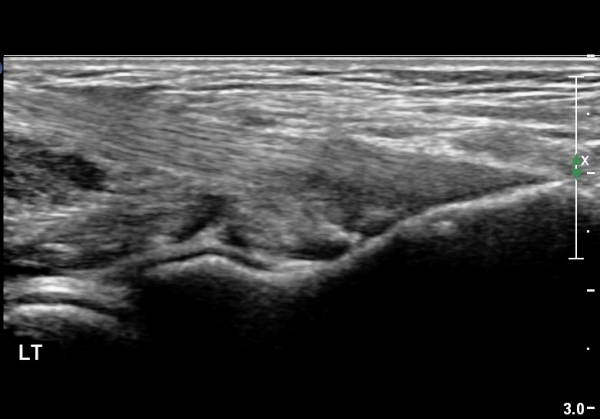

¿ìÃø ÆÈ²ÞÄ¡ ¾ÕÂÊ¿¡¼­ ÀÌµÎ¹Ú±Ù°Ç È¾´Ü¸é°Ë»ç¿¡¼­ À̵ιڱٰǿ¡ ƯÀÌ ¼Ò°ßÀ» º¸ÀÌÁö ¾Ê(±×¸² 1, 2).